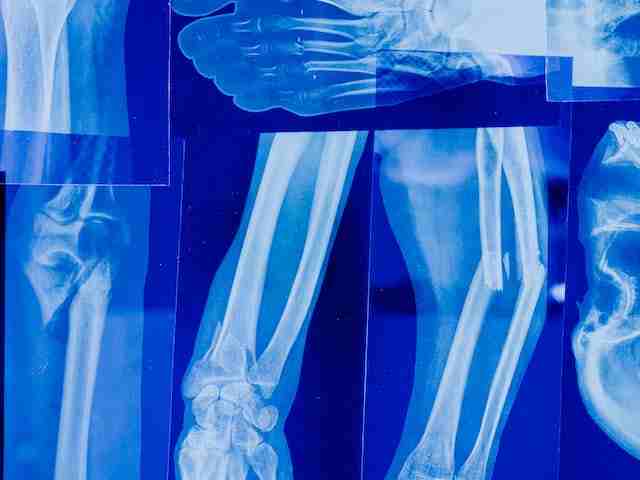

ऑस्टियोपोरोसिस के कारण, लक्षण व इलाज Osteoporosis in Hindi

यहाँ पढ़ें: ऑस्टियोपोरोसिस के कारण, लक्षण, बचाव, रोकथाम, और इलाज – Osteoporosis ke Karan, Lakshan, ilaj, Symptoms, Causes, Prevention, Treatment in Hindi.

आर्थराइटिस (गठिया) के प्रकार, लक्षण, इलाज Arthritis in Hindi

आर्थराइटिस (गठिया) के प्रकार, लक्षण, और इलाज – Arthritis (Gathiya) ke Prakar, Lakshan, aur ilaj – Arthritis Symptoms & Treatment in Hindi – संधिशोथ की पूरी जानकारी आपको इस लेख में मिलेगी|